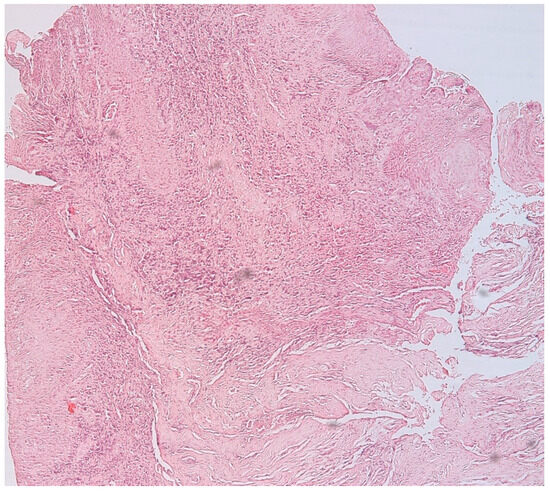

3.1. Morphologic Analysis

3.2. Mast Cells

3.3. Aspects of Microvessels